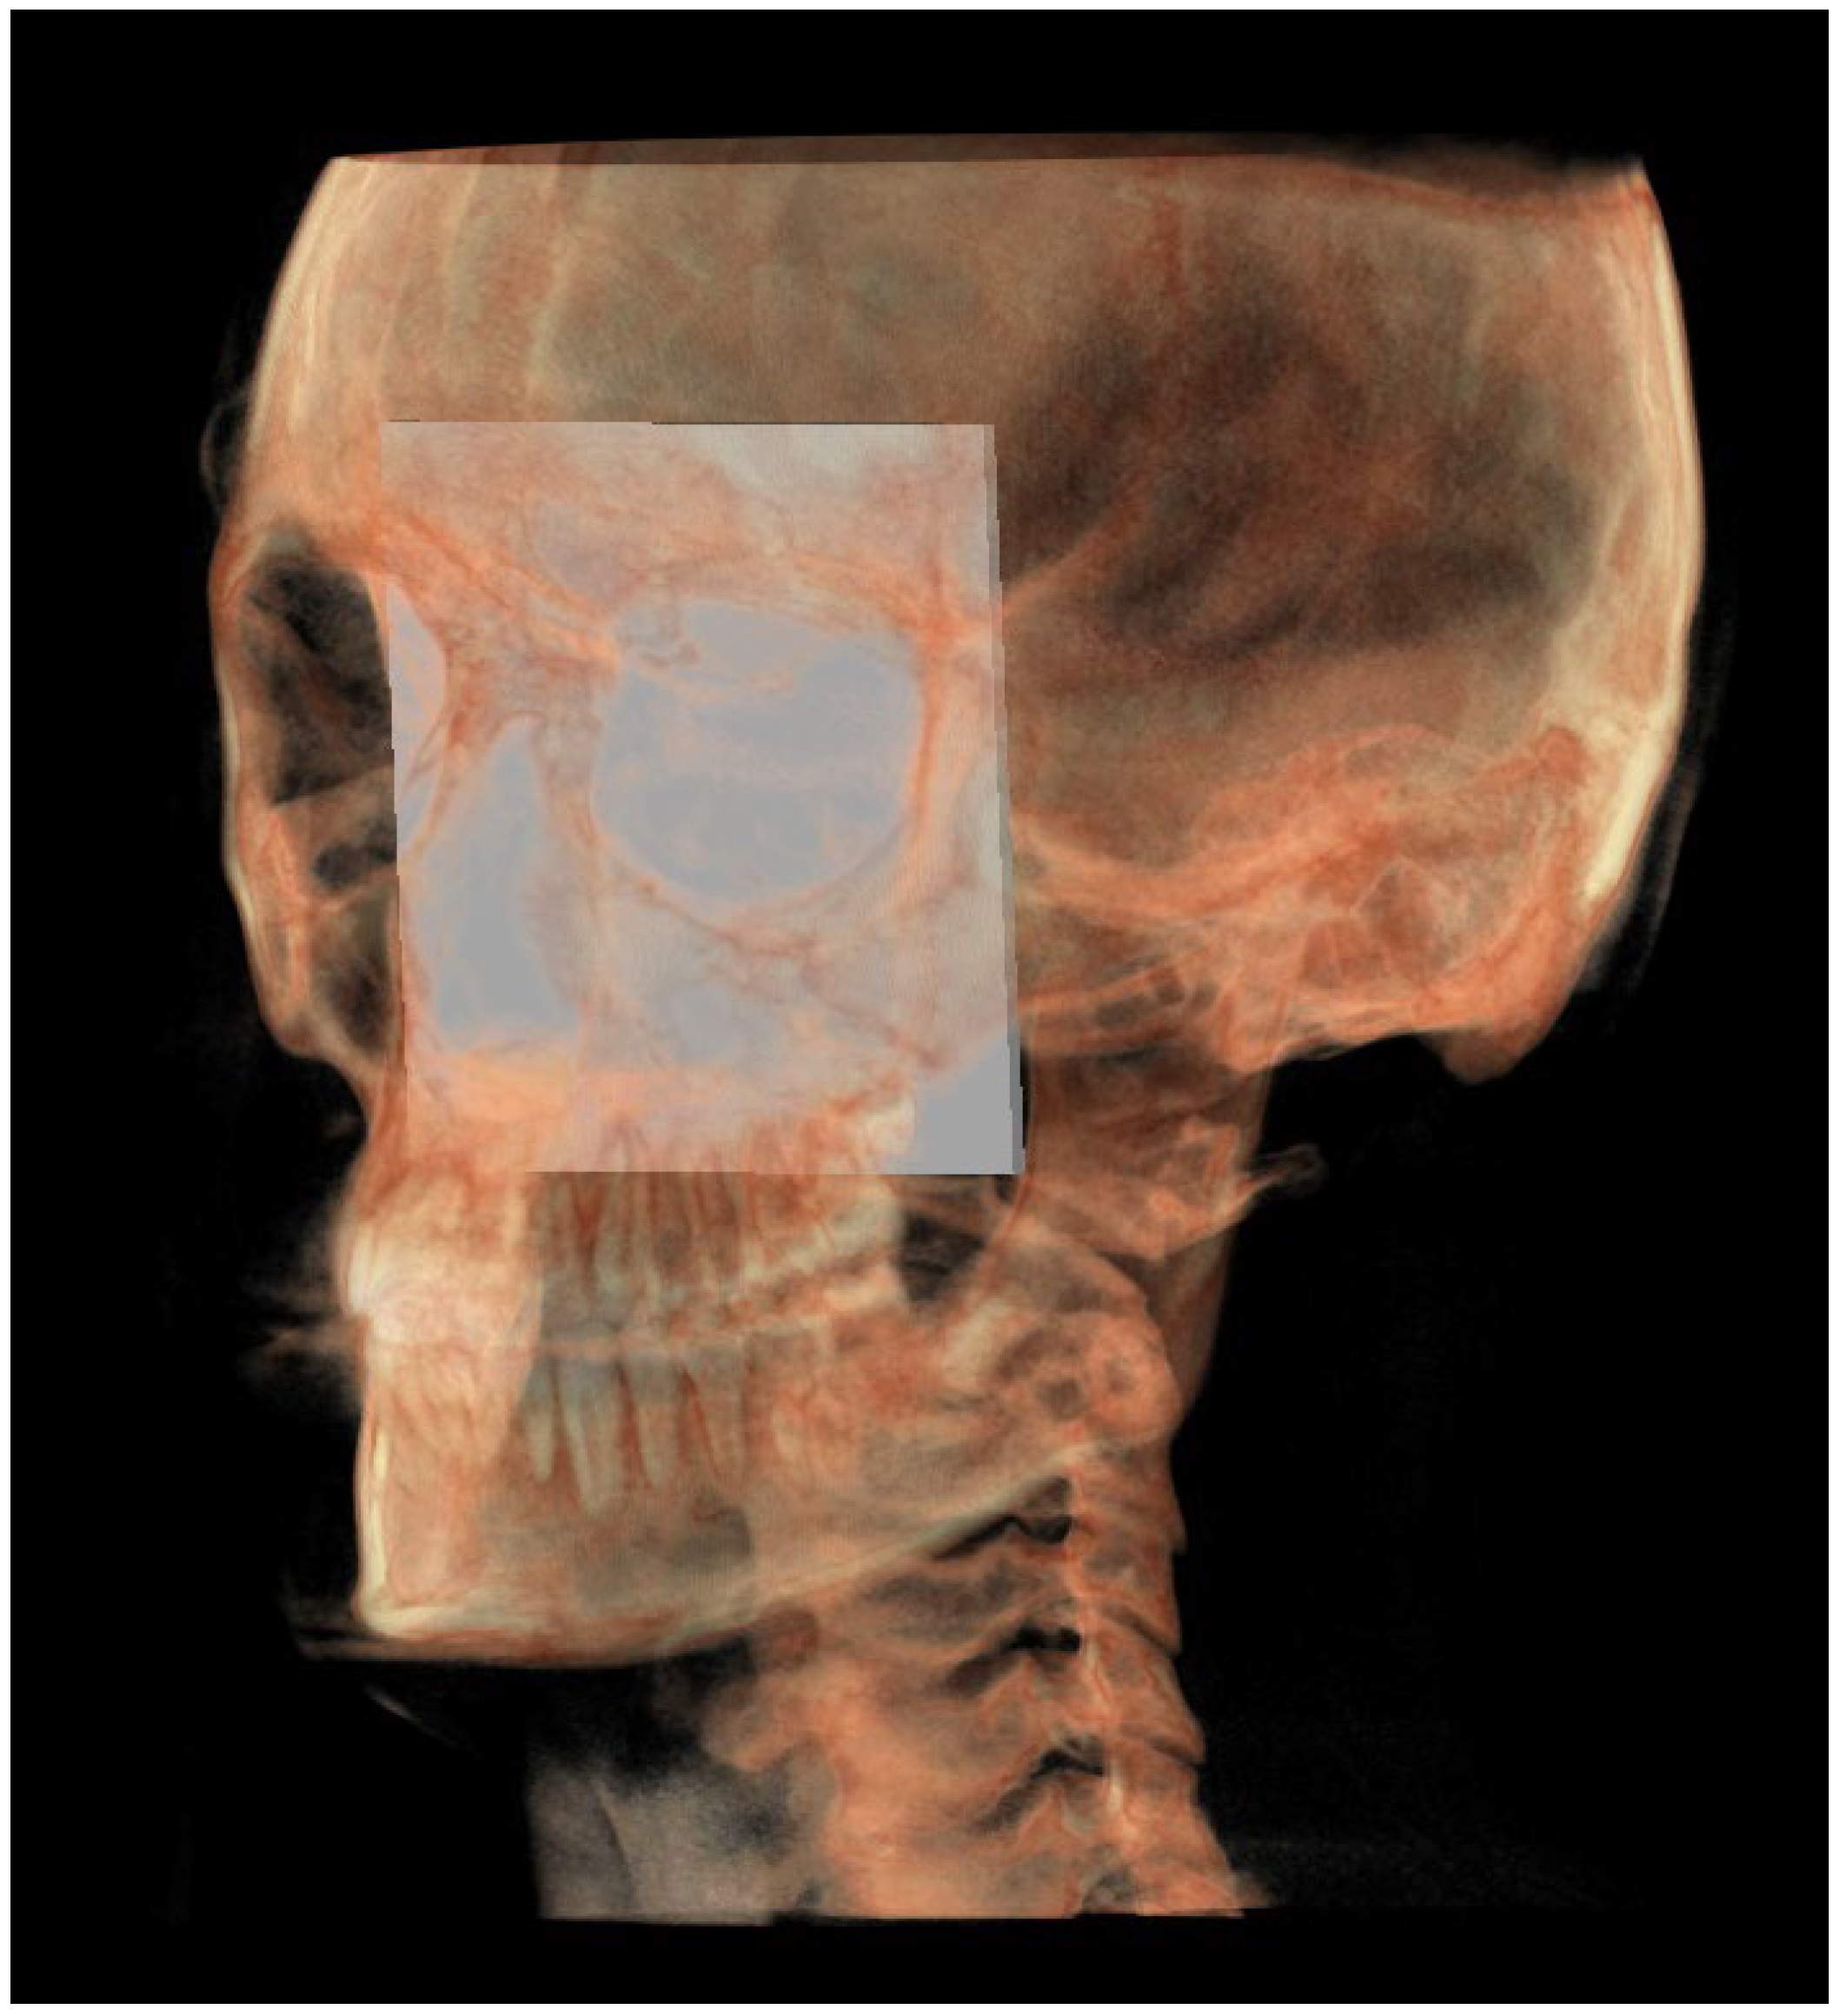

| Right condylion (rCo) | Most posterior point of mandibular condyle, right side | Most posterior point of mandibular condyle, right side | Most posterior point of mandibular condyle, right side |

| Left condylion (lCo) | Most posterior point of mandibular condyle, left side | Most posterior point of mandibular condyle, left side | Most posterior point of mandibular condyle, left side |

| Middle point between right and left Co (mCo) | Middle point between the two condylion | Middle point between the two condylion | Middle point between the two condylion |

| Right gonion (rGo) | Point at inferior border of mandibular angle at mid-distance between posterior-inferior-most point of ramus and inferior-posterior-most point of mandibular body, right side | Middle-posterior-most point of mandibular angle, right side | Middle-inferior-most point of mandibular angle, right side |

| Left gonion (lGo) | Point at inferior border of mandibular angle at mid-distance between posterior-inferior-most point of ramus and inferior-posterior-most point of mandibular body, left side | Middle-posterior-most point of mandibular angle, left side | Middle-inferior-most point of mandibular angle, left side |